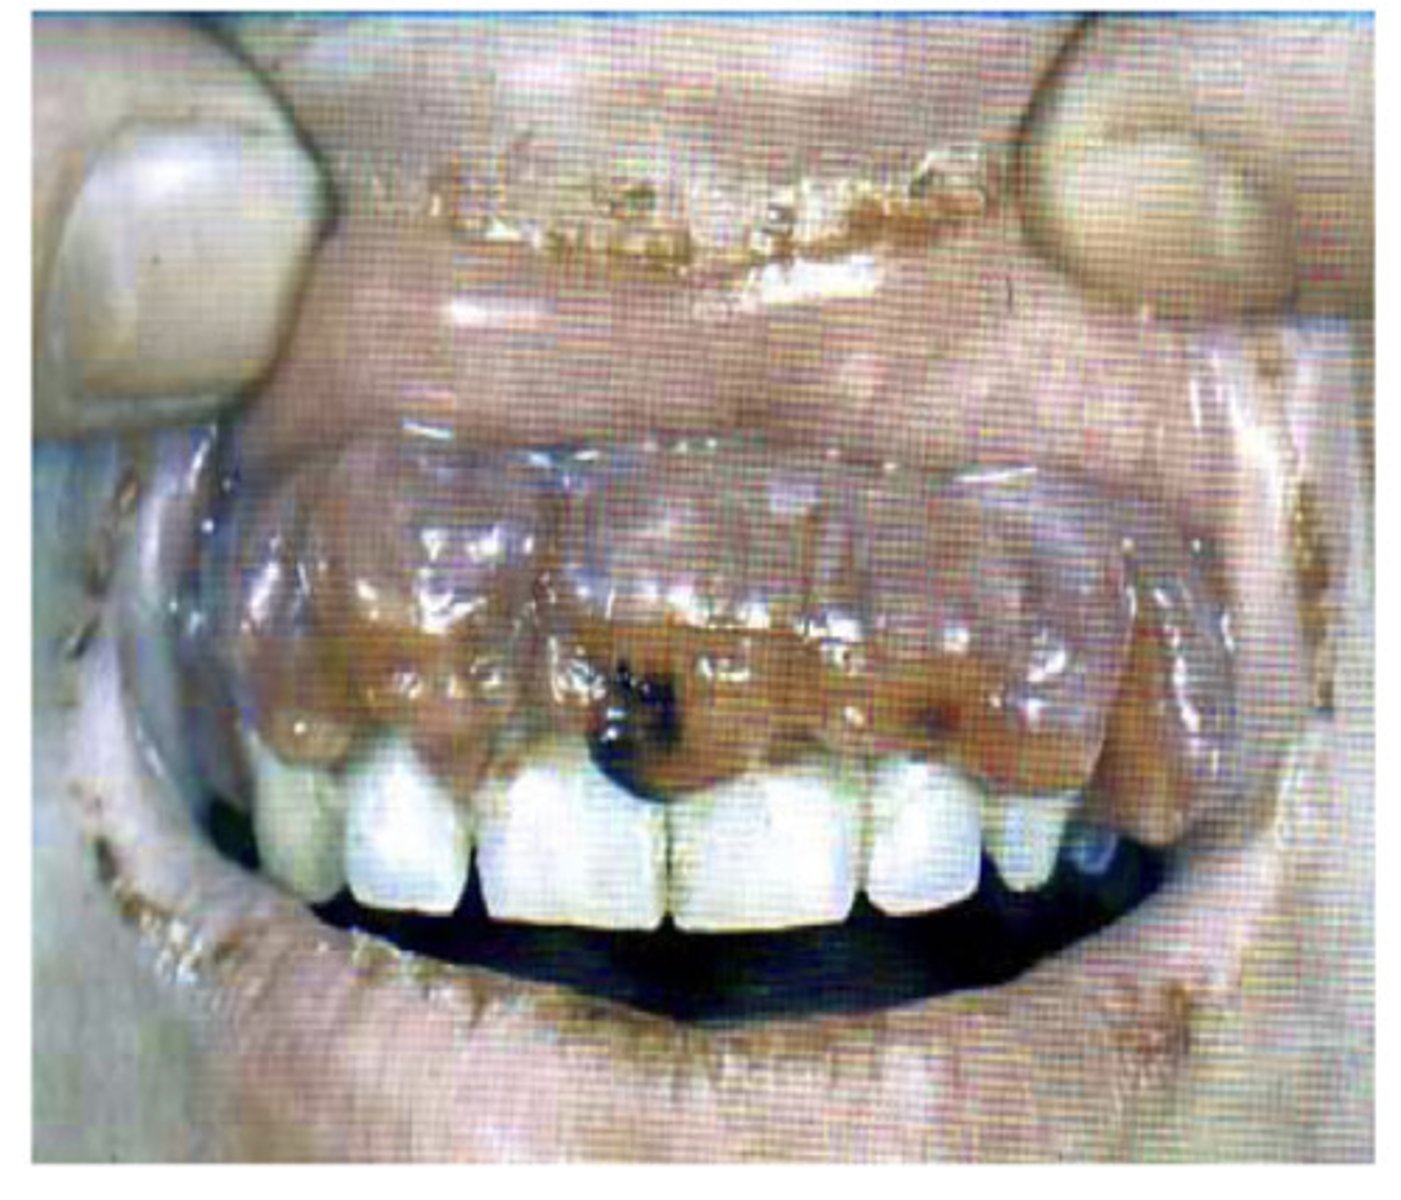

Denture hyperplasia

What is this?

Associated with chronic irritation - treatment is excision and creation of a new applicance